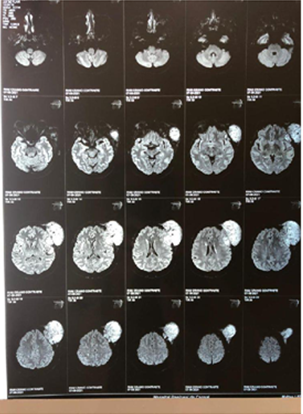

Figure 2A Contrast-enhanced magnetic resonance imaging showing a tumor in the extraaxial region of left frontal involvement.

Figure 2B Contrast-enhanced magnetic resonance image showing a tumor in the extraaxial region of left frontal involvement.

Figure 5A Contrast-enhanced magnetic resonance image showing a tumor in the extraaxial region of left frontal involvement with axial section.

Figure 5B Contrast-enhanced magnetic resonance imaging showing a tumor in the extraaxial region of left frontal involvement.